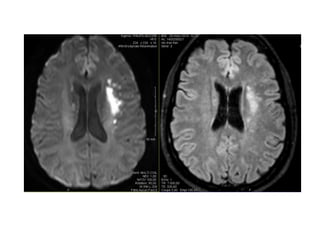

Mismatch diffusion-FLAIR

• Infarctus sylvien gauche étendu

• Présence d’un mismatch Diffusion/FLAIR

• 29 ans •Infarctus sylvien gauche étendu • De cause cardioembolique • Présence d’un mismatch Diffusion/FLAIR MAIS